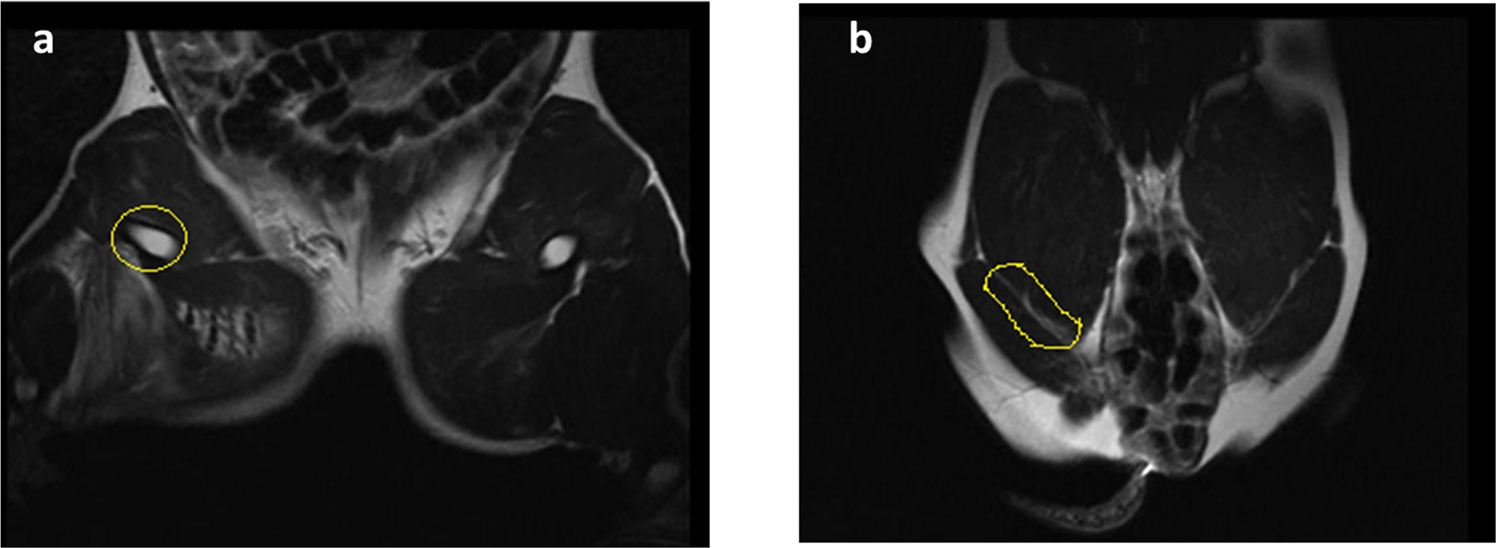

Figure 2

Representative MRI of the arterial circulation in the hind legs of surviving animals treated with CF and CS dressings 3 hours after surgery (a,b). Note that the blood flow in the treated femoral artery was not affected (yellow circle).